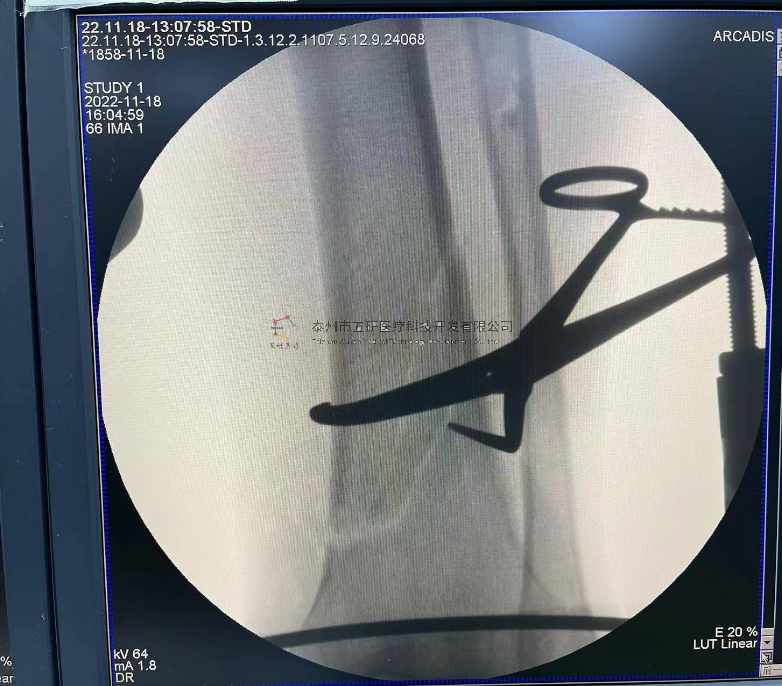

// 下肢骨折

【所屬科室】中國(guó)中醫(yī)科學(xué)院望京醫(yī)院創(chuàng)一科

【基本資料】患者,男,65歲

【患者情況】脛骨遠(yuǎn)端骨折伴腓骨骨折

【影像圖片—術(shù)后】